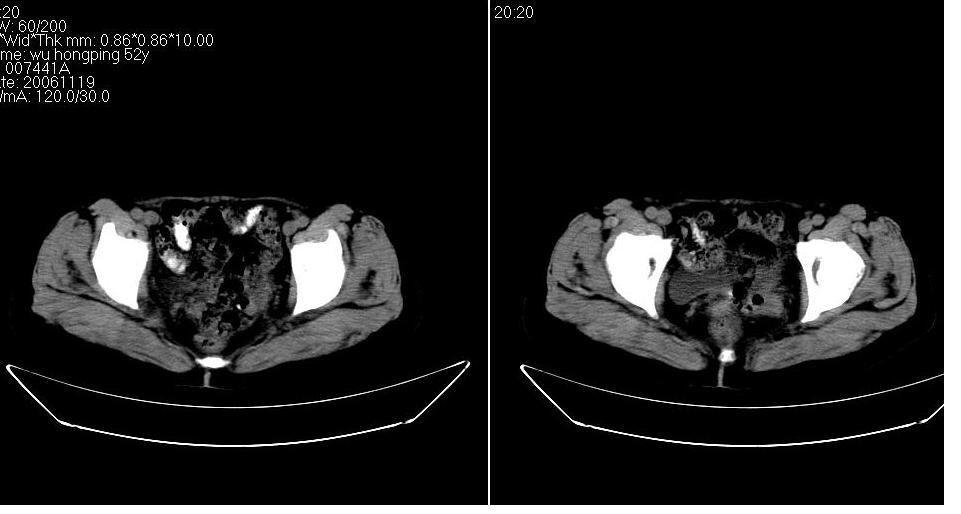

双侧盆腔均可见不规则形软组织肿块影,似为结节状影融合而成,但以右侧为甚,腹主动脉与下腔静脉周围亦可见多个肿大淋巴结.

结合临床手术史考虑:盆腔与腹膜后多发性淋巴结转移(原发灶可能是原来的\"子宫肌瘤\"恶变或并非\"子宫肌瘤\";回盲部肿瘤不排除)

支持。大便次数多可能系腹膜后肿大淋巴结累及肠腔所致。另外,可钡灌肠检查,进一步观察直肠及其他结肠有否异常。